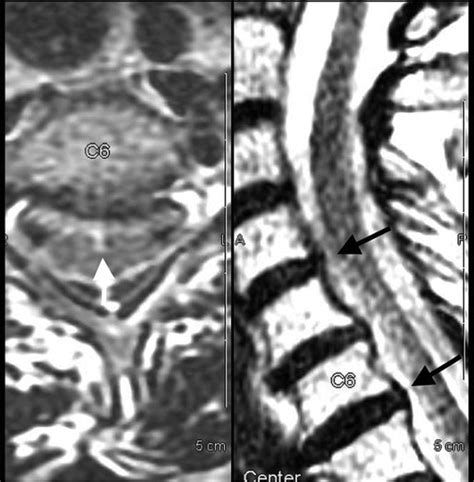

The anterior fissure spinal cord is a longitudinal groove that runs along the anterior (front) surface of the spinal cord. This fissure is a prominent anatomical landmark that helps in identifying the anterior median sulcus, which is a shallow groove that runs along the midline of the anterior surface of the spinal cord. The anterior fissure is continuous with the anterior median fissure of the medulla oblongata, which is part of the brainstem.

The anterior fissure is significant because it marks the boundary between the left and right halves of the spinal cord. It is also the site where the anterior spinal artery runs, providing blood supply to the anterior two-thirds of the spinal cord. This artery is crucial for the functioning of the motor neurons and the sensory pathways that transmit pain and temperature sensations.

• Diagnostic Imaging: Magnetic resonance imaging (MRI) and computed tomography (CT) scans can be used to visualize the anterior fissure and assess its integrity. These imaging techniques are essential for diagnosing spinal cord injuries and neurological disorders.

• Imaging Techniques: MRI and CT scans are essential for visualizing the spinal cord and the anterior fissure. These imaging techniques can help identify structural abnormalities, such as tumors or fractures, and assess the integrity of the anterior spinal artery.